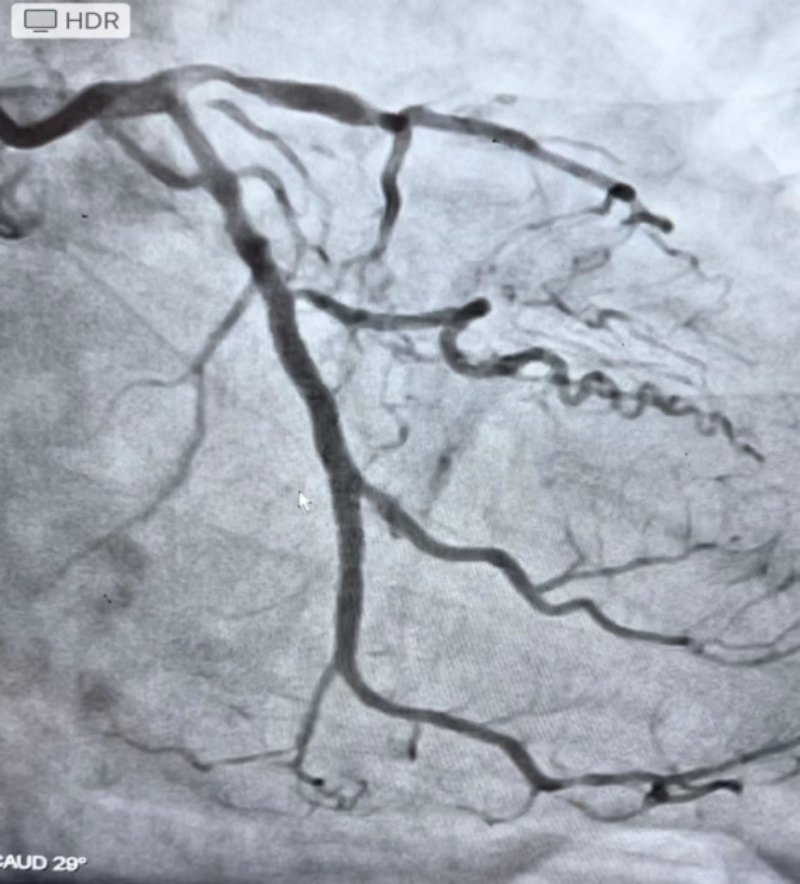

据患者罗阿姨介绍,她曾多次因胸闷痛在南溪山医院住院治疗,3年前进行冠脉造影时就提示她的冠脉严重狭窄并近段完全闭塞,当时进行近段冠脉支架植入后症状得到了缓解。但近半年来,症状又频繁发作,只能再次就诊,冠脉造影提示她的冠脉近段支架通畅,然而远段血管99%闭塞并且伴有严重钙化。医生尝试用导丝通过病变后,使用目前最小的1.0mm球囊进行扩张。

遗憾的是,因病变硬化极为严重,经过反复尝试均未能成功通过,而规范的冠心病药物治疗仍不能缓解患者的心绞痛。因此,朱汉华博士决定尝试冠脉准分子激光消蚀术这一新技术来解决此难题。

2.术前影像。医院供图